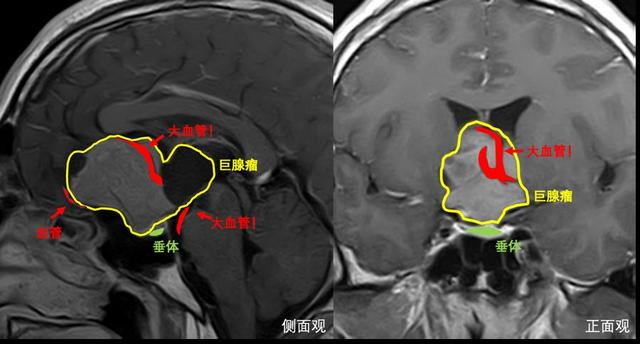

两年前浩宇在两个月内暴瘦40斤,血糖飙升至20mmo/L。接受对症治疗期间,他与病友交流被告知,鼻子、嘴巴、手脚渐渐肿了起来,可能是垂体瘤。经当地医生检查发现:浩宇真的长了一颗足足有5公分大的脑瘤,肿瘤形态并不规则,呈菜花状,侵犯到脑内的多个腔隙,用“张牙舞爪”来形容真的一点也不过分。这个脑瘤正是浩宇发生变化的罪魁祸首。肿瘤分泌过多生长激素,导致全身多器官都出现变化:血糖居高不下、肢端肥大……医生表示,如果任由肿瘤发展下去,患者寿命要比正常人至少少10年。

王镛斐介绍:以往对此类肿瘤都是采取先开颅手术,过段时间后再进行经鼻手术切除,患者需要经受两次手术,时间、精力和财力投入都比较大。开颅手术会造成疤痕粘连,也为再次经鼻手术切除肿瘤造成一定困难。此次采用的“上下联合入路”同时需要两组手术医生,分别采取开颅和内镜经鼻的方法切除肿瘤,两组医生相互配合下可以实现优势互补,能最大程度地保证安全地切除肿瘤。

“上下联合入路”手术方案对团队技术有极高的要求,也对医生的协作配合提出了巨大挑战。做好充分准备后,手术按照既定规划有条不紊开始。王镛斐负责内镜经鼻手术,从下方捣毁肿瘤根基,寿雪飞副教授负责开颅手术,从上方挖取肿瘤顶部。幸运的是,在药物治疗后,肿瘤血供明显减少,这让医生在切除肿瘤时更好地控制出血量,避免大量失血。对于钻进各腔隙内不易切除的肿瘤,寿雪飞通过将其向下推挤,使其暴露在视野内,王镛斐则趁机将此部分肿瘤从下方挖出,8个小时精诚合作下,肿瘤被全部切除。